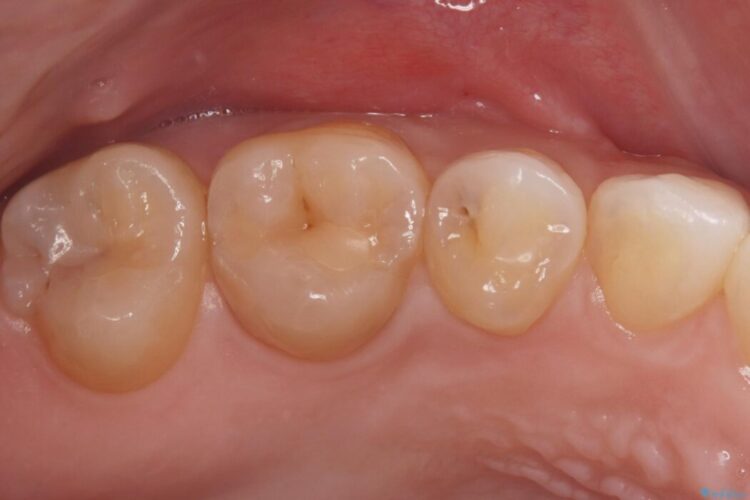

自然な見た目のセラミックインレーで精密に修復 ビフォー 自然な見た目のセラミックインレーで精密に修復 アフター

右上5番に小さな穴があるとご相談にいらした患者様です。